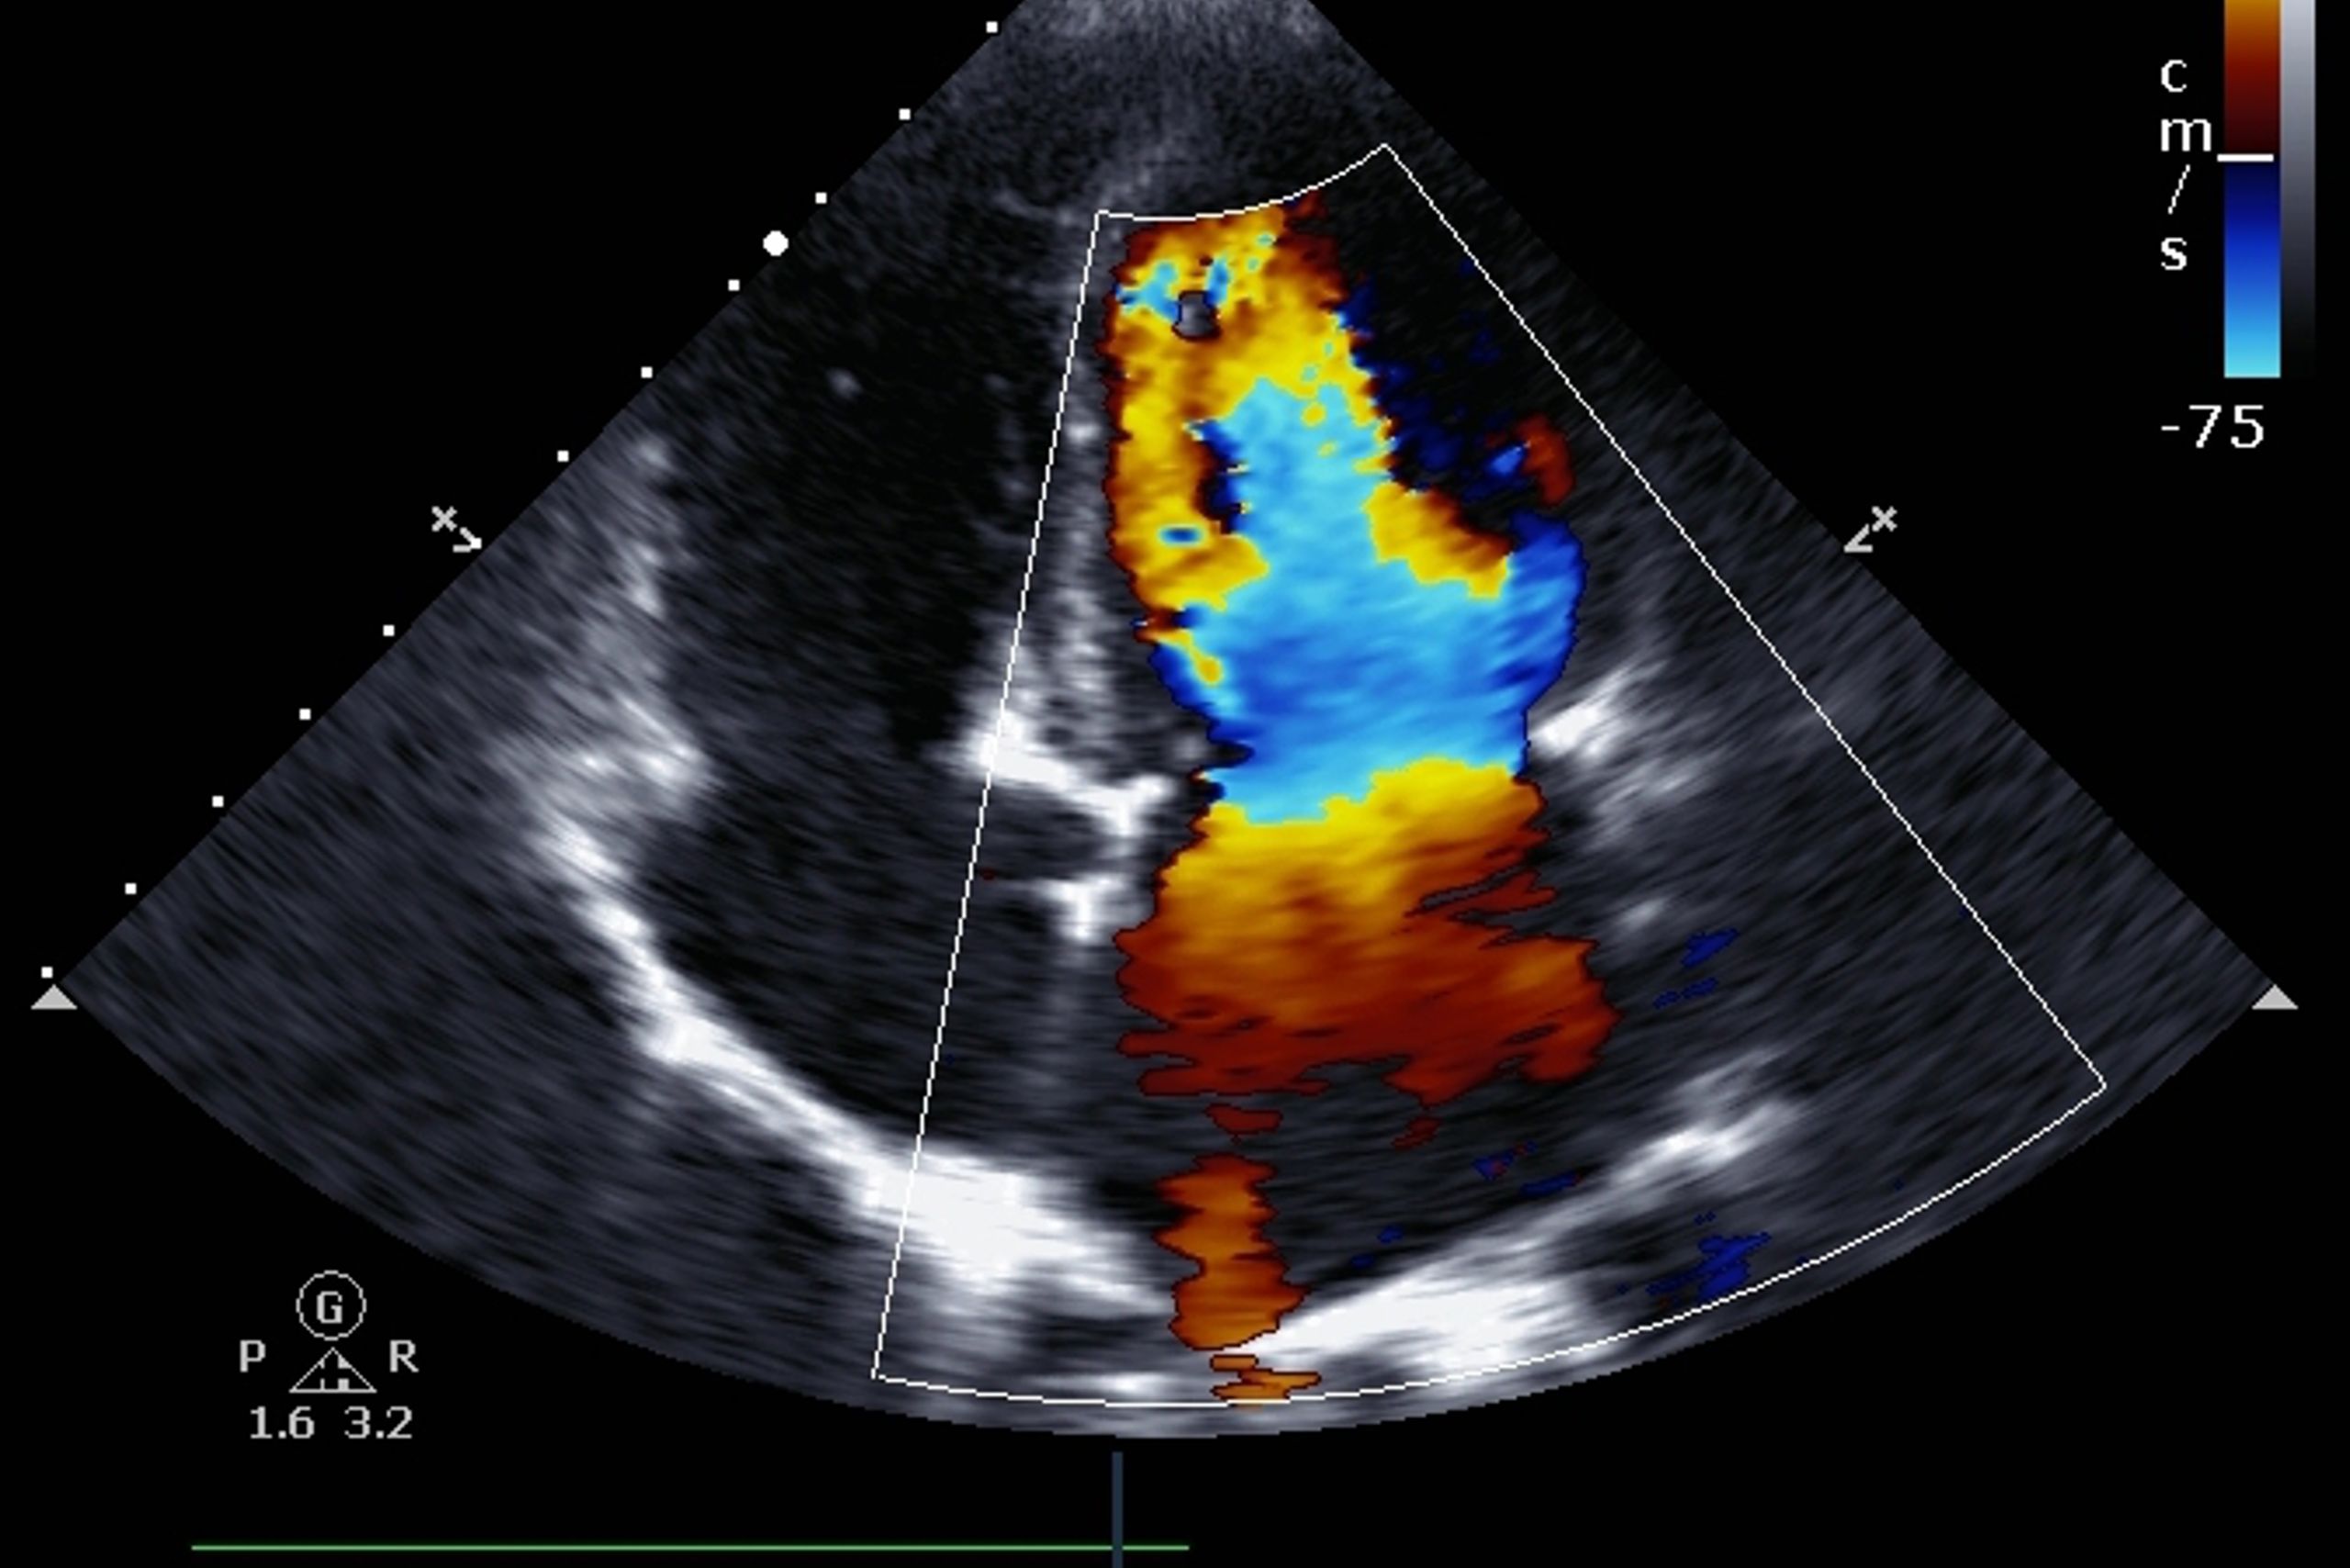

El ecocardiograma 2D con Doppler color es una prueba cardiológica avanzada que realizo para estudiar el corazón en movimiento y valorar con precisión su estructura y funcionamiento. A través de esta técnica puedo analizar las cavidades cardíacas, la fuerza de contracción del músculo y el estado de las válvulas, así como observar cómo circula la sangre en su interior.

El Doppler color aporta información clave sobre el flujo sanguíneo, permitiendo detectar alteraciones como fugas valvulares, estrechamientos o cambios en las presiones intracardíacas.

El ecocardiograma 2D con Doppler color es una de las pruebas más completas para valorar el corazón. Me permite estudiar no solo la forma y el movimiento del corazón, sino también cómo circula la sangre en su interior, algo fundamental para detectar muchas enfermedades cardíacas.

Estudiar el flujo sanguíneo mediante Doppler color